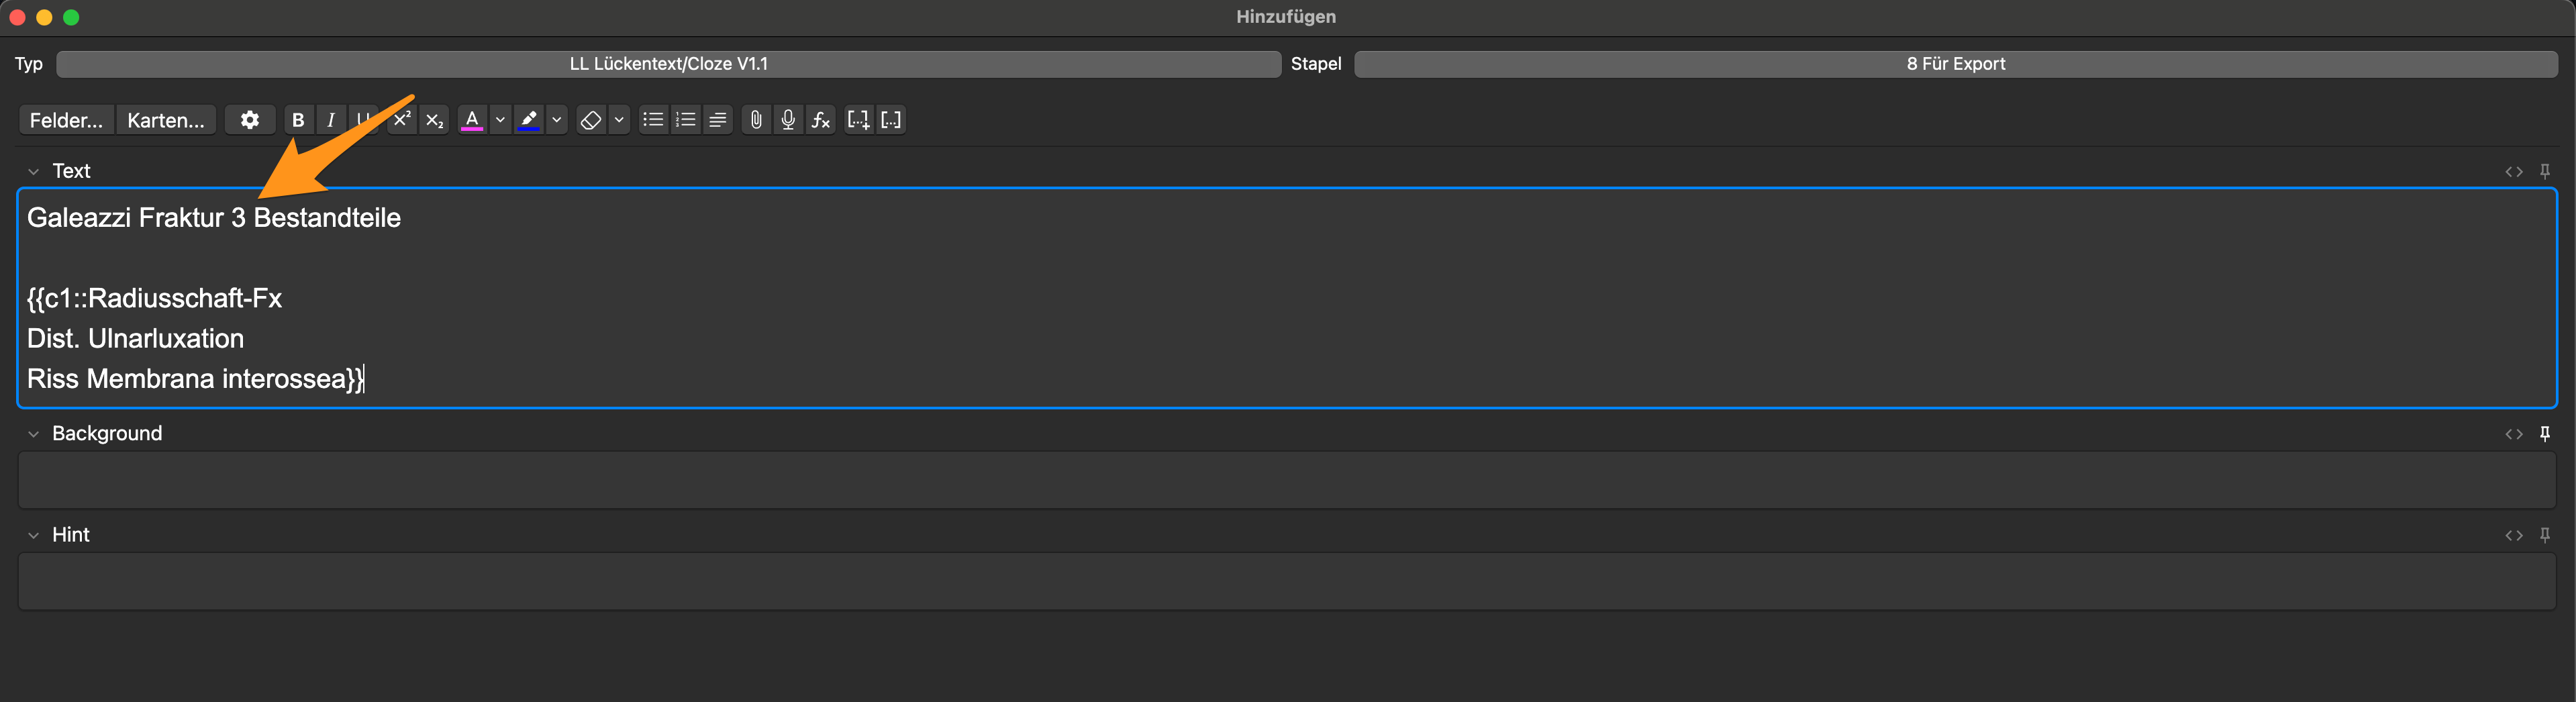

- Defi.: Bestandteile eines medizinischen Terminus – z. B. Galeazzi-Fraktur

Wenn dadurch mehrere Items abgefragt werden, sollte die Anzahl kenntlich gemacht werden, um deinem Gehirn eine komfortable mentale Antwort-Fahrbahn zu ermöglichen:

Die abzurufende Information „3 Bestandteile“ kann auch in Blau in der Klammer vor Beantwortung der Frage dargestellt werden. Dazu ::3 Bestandteile hinter die Antwort einfügen (der :: erlaubt diese Funktion). Das ist eine Präferenzfrage; ich mache es gerne so:

Weiteres Beispiel: